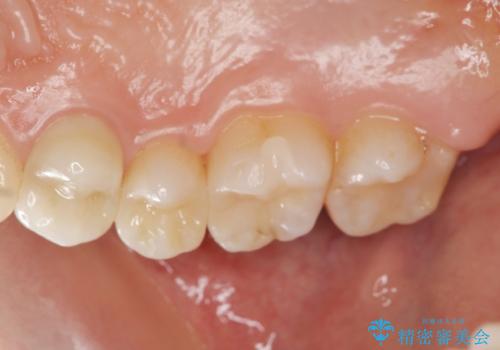

以前治療した歯が痛む 銀歯をセラミックに

- 27万円(セラミックインレー×2 仮歯・ファイバーコア・ジルコニアクラウン)費用は治療当時の料金となります

虫歯治療は小さい場合にはセラミックインレー、大きな場合や痛みが生じている場合は根管治療ののちクラウンによる機能回復が必要となることが多いです。